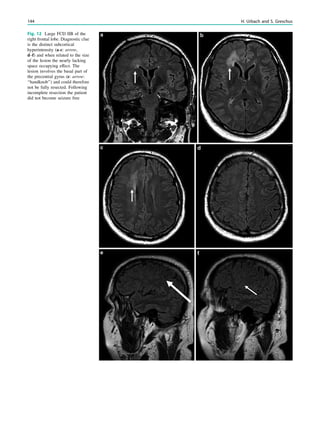

Fig. 2 Dural a. v. fistula. A 53-year-old man presented with two tonic–

clonic seizures. MRI shows circumscribed edema in the left frontal lobe

(a, hollow arrow) and an abnormal vessel running in the left sulcus

rectus (c, arrow). The digital subtraction angiogram of the left internal

carotid artery shows a frontobasal dural arteriovenous fistula fed via

ethmoidal arteries (d, arrow) and confirms the abnormal vessel as a

draining vein (e, arrow)